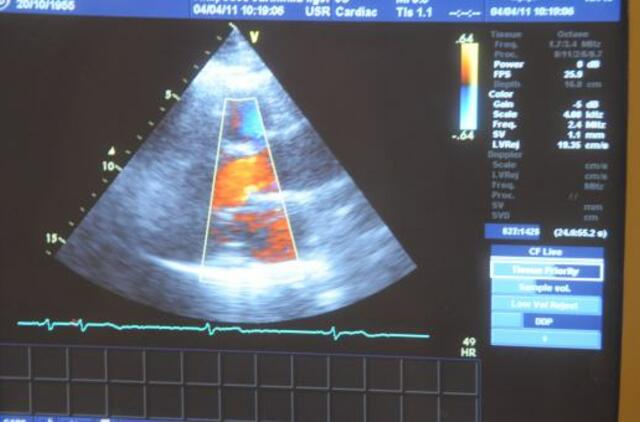

Džojui Skeratui (Joe Skerratt) iš Kento grafystės buvo diagnozuota dilatacinė kardiomiopatija - širdies veiklos sutrikimas. Tai reiškė, jog vaiko širdis buvo per silpna varinėti kraują po kūną.

2010-ųjų gruodį gydytojai pastebėjo, jog sutriko vaiko širdies veikla. Praėjus kelioms dienoms berniuko širdis sustojo dukart, o perkėlus jį į vaikų ligoninę "Great Ormond Street Hospital" Londone širdis sustojo dar kartą. Tada gydytojai stabilizavo Džojaus sveikatos būklę, pasinaudodami dirbtinių širdies skilvelių Berlyno širdimi.